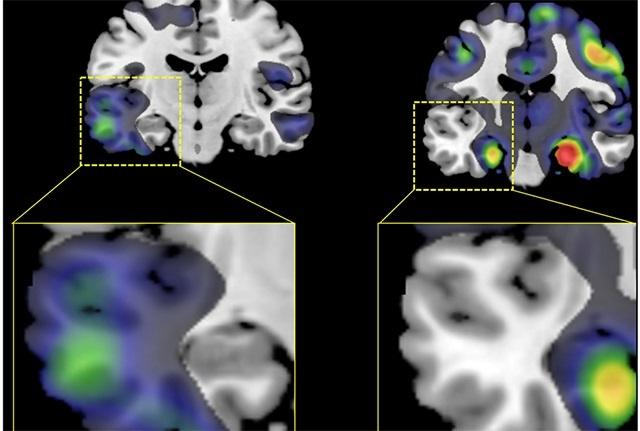

The researchers found that the volume of gray matter was lower — a sign of atrophy — in different regions of the brain depending on the subtype of the disease afflicting the patient. Those in the AD-Memory subtype, for example, had lower volumes in an area known to be crucial for learning and memory, called the medial temporal lobe, while the rest of the brain was relatively spared. Those in the AD-Visuospatial subtype, on the other hand, had lower volume in the gray matter toward the back of the head, where visual information is processed. Those with the AD-Executive functioning subtype had lower volume in the front of the brain, in areas where planning, judgement and other higher-order functions are known to reside.

Of particular interest was the finding that lower volumes were strikingly asymmetrical in patients with the AD-Language subtype compared with those in any other subgroup or to the normal controls. In these patients, atrophy was notably greater on the left side of the brain than on the right.